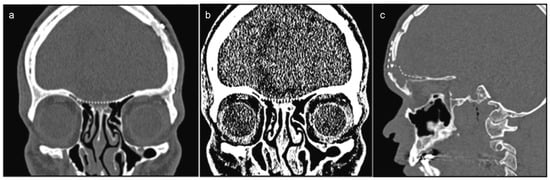

A 26-year-old male patient with a history of motorcycle accident presented with trauma in the naso-orbital-ethmoid region. The patient’s Glasgow coma scale score was 13/15 upon admission to the emergency room. Clinical examinations revealed CSF rhinorrhea, frontonasal sinking, and anosmia (Figure 1a). Computed tomography (CT) demonstrated multiple facial fractures, skull base defect in the cribriform plate region, and fractures of the posterior wall of the frontal sinus (Figure 1b–d and Figure 2a–c).

Figure 1. (a) A 26-year-old male patient with CSF rhinorrhea, frontonasal sinking caused by a motorcycle accident. (bd) Computed tomo-graphic scans showed a facial fractures, skull base defect in the cribriform plate region.

Figure 2. (a,b) Three-dimensional volume rendering images showing the forehead deformity and retrusion. (c) The size of the skull base defect.